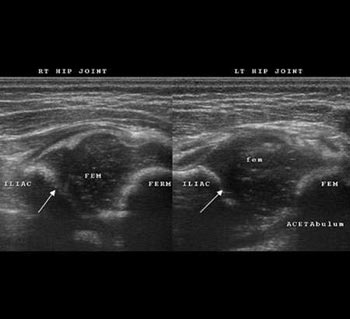

A case of right sided congenital dislocation of hip with flat right sided acetabulum (arrows) and lateral subluxation of small sized right head.